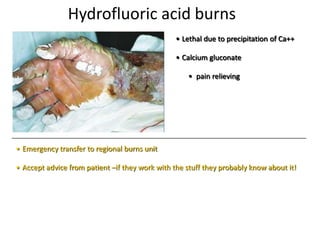

- Conditions that require emergency referral are discussed, such as bleeding, amputation, replantation, compartment syndrome, infections, and high pressure injection injuries. Proper management of these conditions focuses on rapid assessment and treatment to prevent further tissue damage.